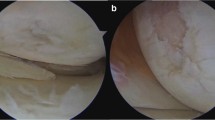

Expression of β-catenin

Staining with β-catenin antibody was weak compared to immunohistochemistry of CD68 and ASMA, which made evaluation on the microscope more difficult. Cytoplasmic expression of β-catenin was observed, cell nucleus and cell membrane showed no staining (Fig. 3). In the synovium of the AF group, expression of β-catenin averaged 2.00, which corresponds to staining of 10–25% of synovial cells compared to a value of 1.00 in the control group. Based on the expression of β-catenin in synovium, a statistically significant difference between AF group and control group was found (p = 0.003). The strongest expression of β-catenin was found in endothelial cells of AF patients, with a median of 4.00 (p < 0.001). An equally high level of β-catenin was seen in fibroblasts of cell-rich fibrosis. With a median expression of 4.00 in the AF group, the difference to the control group was statistically significant (p < 0.001). In areas of low-cell fibrosis of the AF group, the expression of β-catenin averaged 1.00, which was also significantly different (p = 0.047) to the control group. In terms of total tissue, the median expression of β-catenin in tissues of AF patients was 2.63 and 1.00 in the control group. Overall, both groups showed a statistically significant difference in expression of β-catenin (p < 0.001). Overall, β-catenin showed the strongest expression compared to CD68, ASMA and BMP-2.

Immunohistochemistry of β-catenin in an AF patient. a Slight staining of the synovial cells, magnification ×40. b Marked staining of endothelial cells, magnification ×40. c Staining in the area of cell-rich fibrosis, magnification ×40. d Weak staining in the area of low-cell fibrosis, magnification ×40

Expression of β-catenin

Membranous and cytoplasmic β-catenin contributes to forming the so-called adherens junctions, which are involved in regulation and coordination of cell–cell adhesion [19]. Intranuclear β-catenin plays a key role in activating the canonical Wnt signaling transduction, which is of paramount importance in the regulation differentiation and proliferation of cells [8]. In the literature, a connection between an increased β-catenin expression and the development of fibrosis has repeatedly been described [20,21,22,23]. The results of the presented study demonstrate predominately cytoplasmic expression of β-catenin, which was significantly increased in synovial cell, in endothelial cells as well as in fibroblast of cell-rich and low-cell areas of AF samples (Fig. 3). The current findings go well in line with observations described by Ruppert et al. also demonstrating a strong cytoplasmic expression of β-catenin in endothelial cells and fibroblasts in AF [7]. In the same way, there was no β-catenin expression detected in the nucleus or the membrane.